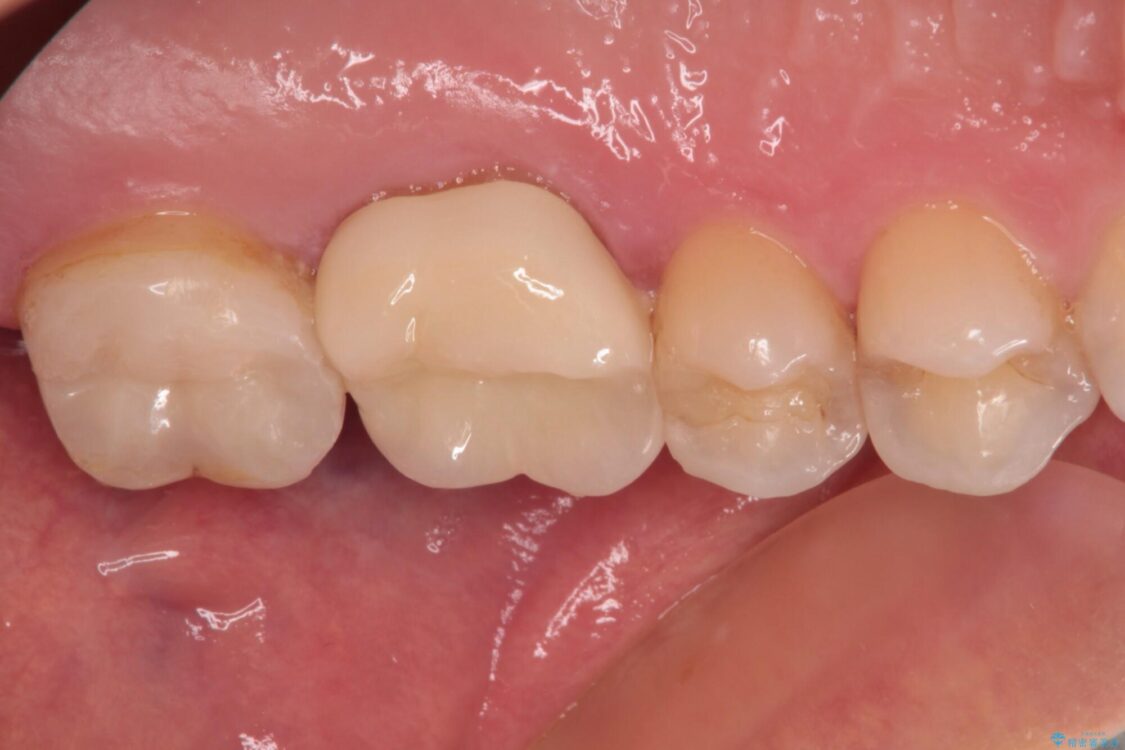

初診時は神経組織の生活反応が認められましたが、2日後に処置を行ったときには、既に反応はなくなっている状態でした。

神経組織は壊死が始まっておりましたが、初回処置後には痛みを感じることもなくなり、2回目に無事に根管治療を終えることができました。

治療後

• 奥歯がズキズキと痛む 奥歯の虫歯治療 治療後画像